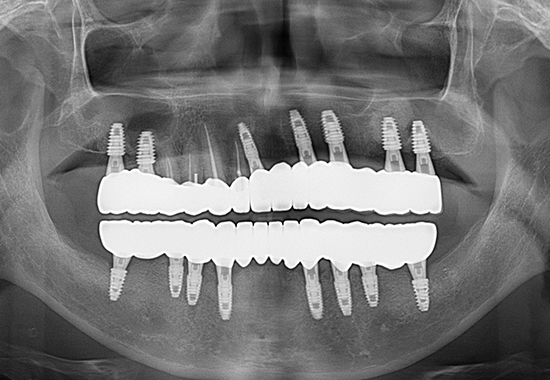

AFTER

- 식립 개수 : 17개 (상악 9개 하악 8개)

- 수술 내용 : 상악동거상술, 치조골 이식